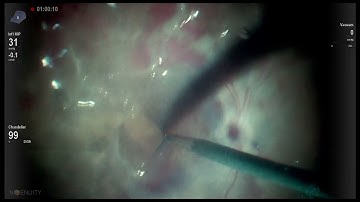

Side by side comparison ILM enhancement filter VS regular view Lukan Mishev